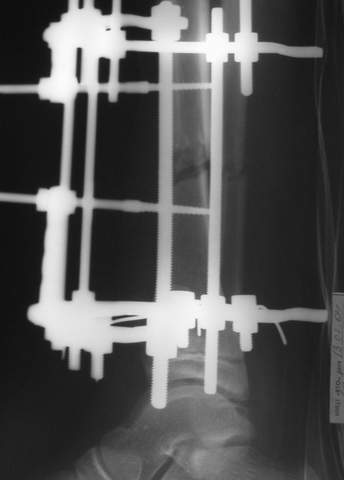

В аттачтах №№ 1 и 2 - примеры, когда 2 кольца не позволили послеоперационно

исправить смещение фрагментов большеберцовой (по ширине и вальгусное).

А казалось бы (#2) - поиграй на штангах и все влетит.

1

1a